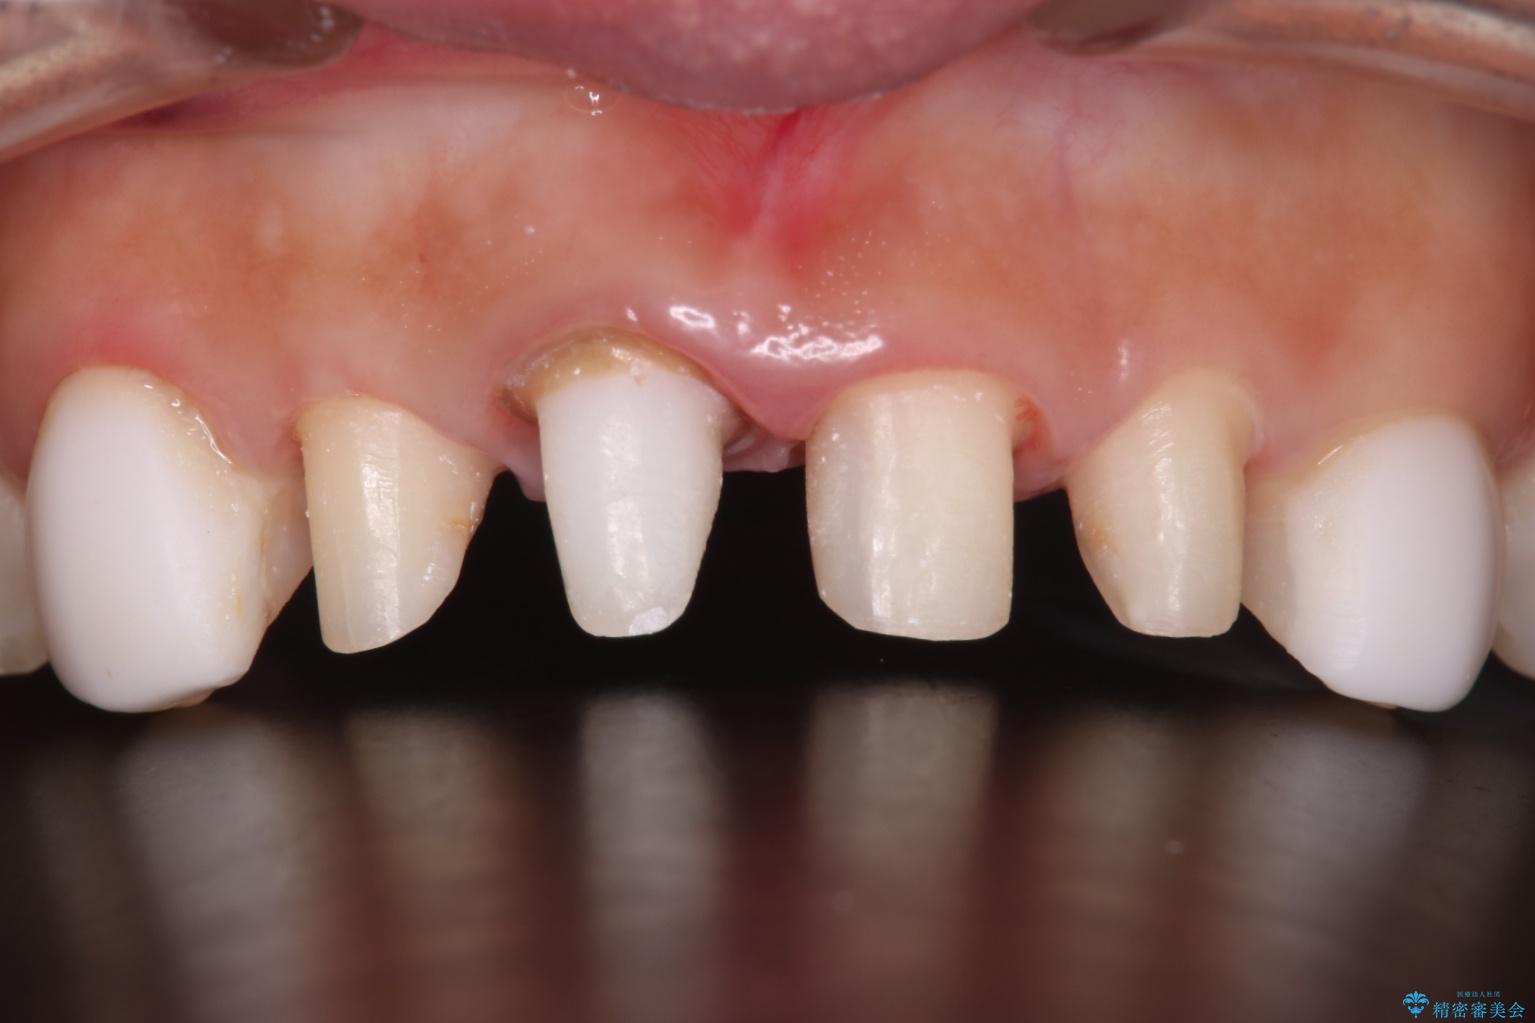

他院で治療した前歯の色が気になるとご来院された患者様です。

前歯の色に差があり、レントゲンで確認すると内部にう蝕も見られました。

審美性に優れ、う蝕になりにくいオールセラミッククラウンで治療することとしました。